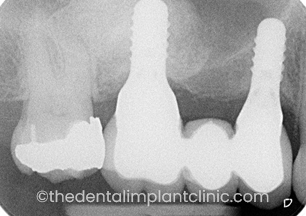

X-Ray of Implants placed at UR2 and UR4 sites

3 Missing back teeth. A sinus lift procedure has been performed to increase the volume of bone available for implant placement at the upper right first molar tooth site (UR6).

Two implants placed at the upper right first premolar site (UR4) and in the sinus graft at the upper right first molar tooth site (UR6).

X-ray picture showing the sinus graft with the implants placed to restore the missing teeth with an implant retained bridge.